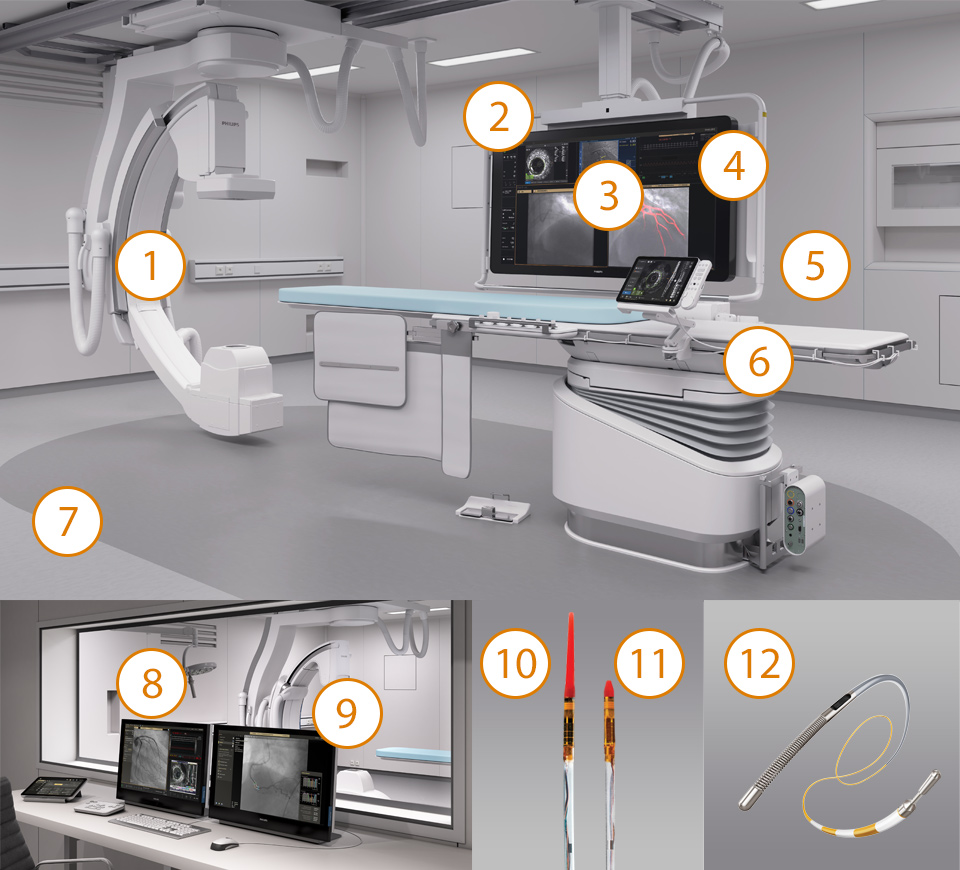

Cómo se combinan nuestras soluciones

La terapia guiada por imagen, iFR, los ultrasonidos intravasculares y la monitorización hemodinámica, así como la planificación previa al procedimiento cardiaco y las aplicaciones avanzadas, están conectados a la interfaz de la terapia guiada por imagen para permitir la visualización, manipulación y configuración personalizada en el monitor desde un único módulo de control en mesa o desde la sala de control.

Sistema de terapia guiada por imagen: Azurion

Azurion permite tratar a un paciente más al día, con lo que se reduce el tiempo del procedimiento en un 17%* con opciones optimizadas para el flujo de trabajo en tratamiento intervencionista y software clínico.

Estación de trabajo con aplicaciones intervencionistas: IntraSight

Proporciona información clínica completa con la perfecta integración de iFR/FFR, ultrasonidos intravasculares y herramientas de reposicionamiento automático que mejoran los resultados sanitarios del paciente.You are about to visit a Philips global content page

Visualización clara, orientación fiable: Dynamic Coronary Roadmap

Orientación de navegación automática en tiempo real diseñada para la eficacia del procedimiento en intervenciones complejas de ICP sin afectar al flujo de trabajo estándar actual.You are about to visit a Philips global content page

Módulo de pantalla táctil TSM pro

Módulo de control de pantalla táctil en mesa intuitivo. Controle de forma continua las aplicaciones compatibles en mesa en el campo estéril con el módulo de pantalla táctil Pro mejorado. Acceda a la fisiología, ultrasonidos intravasculares, mediciones hemodinámicas, herramientas intervencionistas y todos los parámetros de adquisición de imágenes para trabajar de manera rápida y decisiva. Controlar estas aplicaciones en la sala de examen puede ahorrar tiempo, reducir el desorden de los equipos y le ayudan a centrarse en el paciente.You are about to visit a Philips global content page

Sistema Interventional Hemodynamic con IntelliVue X3

Aporta mediciones hemodinámicas avanzadas al laboratorio de cateterismo. Se integra con el monitor de paciente Philips IntelliVue X3 para la monitorización continua del paciente antes, durante y después de la intervención.You are about to visit a Philips global content page